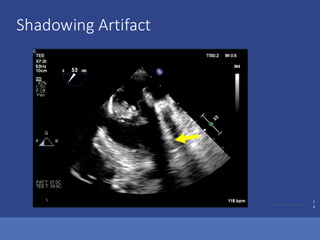

Shadowing Artifact

Ultrasound Assumption Violations Anotherway to think about these Axial Direction Artifacts located below the real Structure Lateral Direction Artifacts located to the side of the real Structure 1.Reverberations 2.Mirror Image Artifacts 3.Acoustical shadowing or enhancement 1.Beam Width Artifacts 2.Side Lobe Artifacts 3.Refraction Artifacts

©2017 Trinity HealthOf New England 1 4 Shadowing Artifact